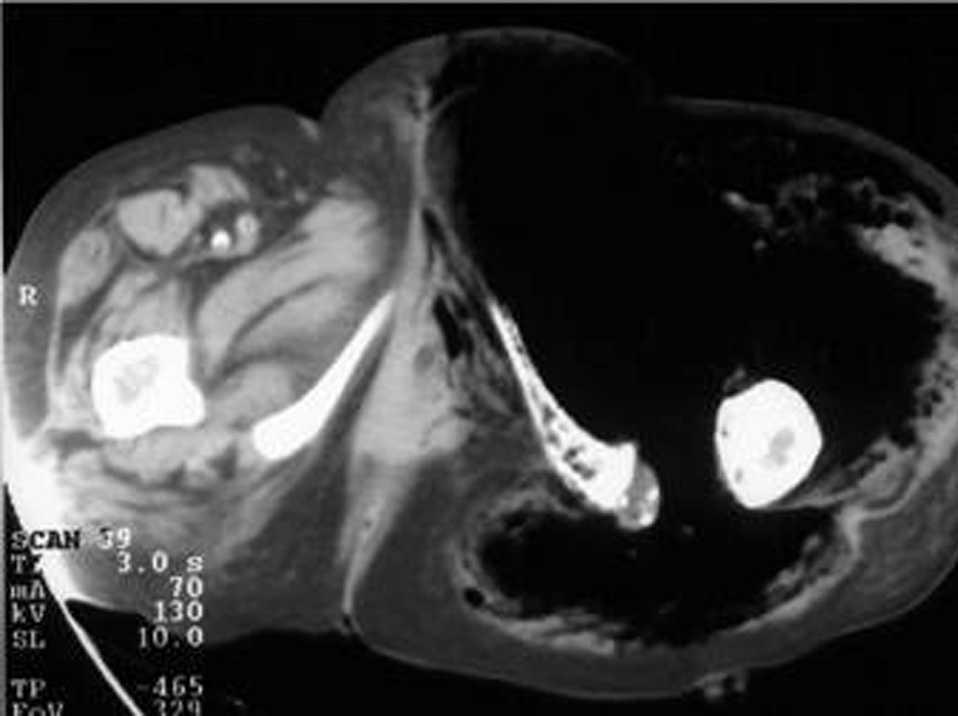

Se procede al desbridamiento quirúrgico con fallecimiento perioperatorio de la paciente. La autopsia evidencia una tumoración yeyunal perforada y adherida al cuerpo uterino como causa del cuadro de gangrena gaseosa (fig. 2). El estudio histopatológico revela un linfoma de células indiferenciadas.

Fig. 2.